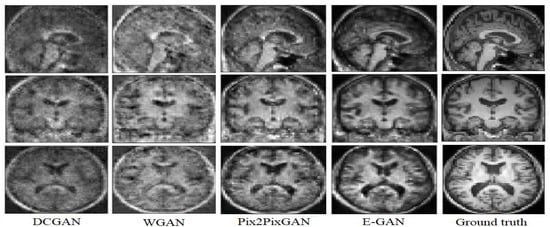

5.3. Tissue Analysis

Gray Level Co-occurrence Matrix (GLCM) is a common texture descriptors. GLCM calculates the Haralick features based on grey level intensities of the image. These features are useful in texture recognition, image segmentation, image classification, and object recognition [36]. In order to evaluate E-GAN in terms of simulating the texture, we have performed the GLCM on the generated images and the ground truth. To do so, each image has been discretized into eight grey levels and the Co-occurrence matrix has been computed for the state of the art methods and the proposed model. Figure 9, shows the Co-occurrence in 3D for a 6o degree angle and distance equal to three as an example. The Co-occurrence matrix of the proposed model is the most similar one to the ground truth Co-occurrence matrix. Pix2Pix GAN also represented a good performance to generate the texture descriptor. In order to have a quantitative assessment of the texture Table 4, represents a comparison of the four most common Haralick features from GLCM for the proposed architecture and the state of the art methods.

Figure 9.

The Co-occurrence matrix DCGAN [35] (A), WGAN [25] (B), Pix2Pix GAN [17] (C), Proposed model (D) and the ground truth (E) in 3D.